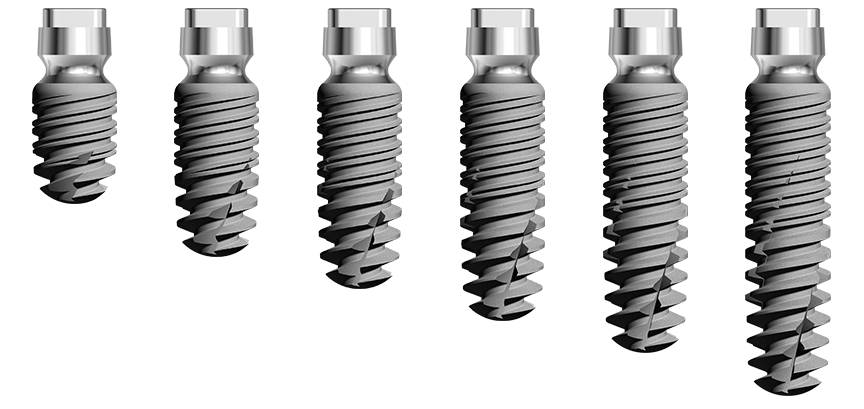

L’implant twinKon® est de type Tissue Level, généralement apprécié pour leur capacité à préserver le capital osseux péri-implantaire(1), mais également pour leur accessibilité prothétique en bouche. Le twinKon® est un implant qui sera particulièrement apprécié en secteur mandibulaire présentant une atrophie allant de modérée à sévère.